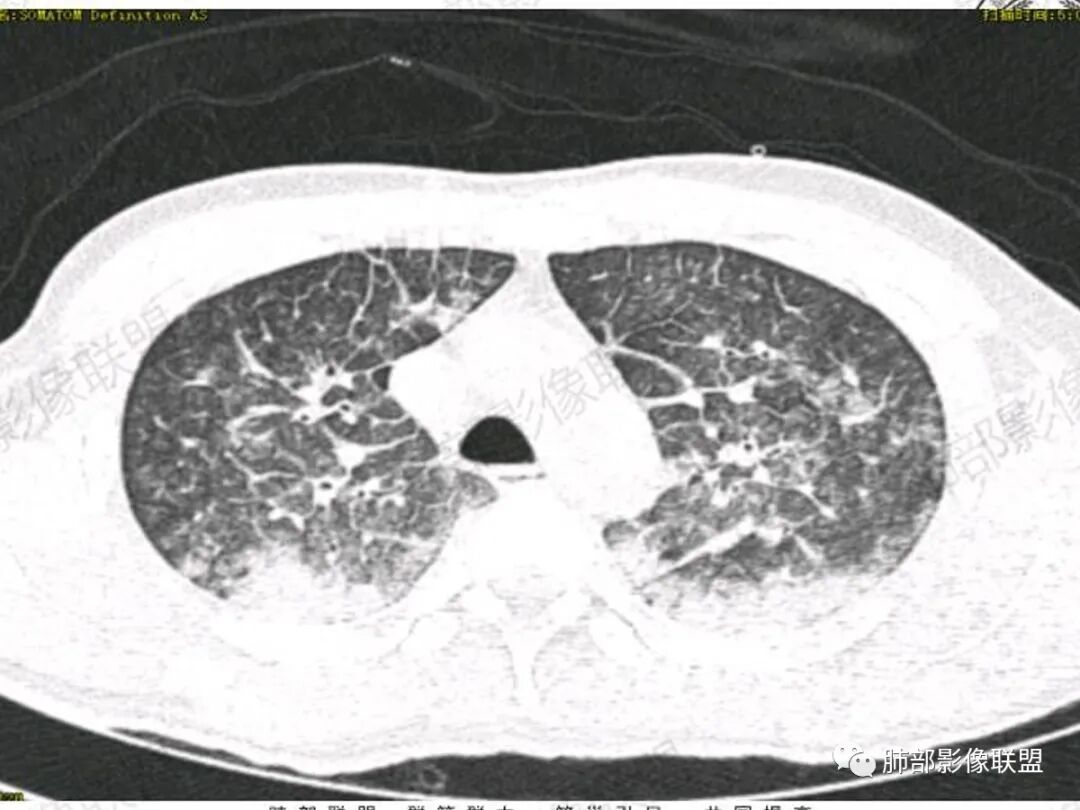

青年男性患者,气促7小时入院,白细胞及中性粒明显增高,PCT增高,CRP不高,心率快,呼吸急促,意识模糊,低氧血症,I型呼吸衰竭,PH偏低,失代偿性酸中毒,BNP偏高,胸部CT:双肺弥漫性多发斑片状实变密度影,双上肺明显,间质改变为主,综合:年轻男性,急性起病,迅速恶化,考虑中毒可能,鉴别:PCP,过敏,

影像学提示肺水肿与肺泡腔液性渗出(小叶间隔增厚+实变+重力趋势),上叶显著。

双肺弥漫性病变以上肺,向心性,背部分布为主,肺动脉干无增粗,急性起病,典型的吸入性肺炎。

既有重力分布特点,也有吸入性特点,这个病例缺乏了特殊病史,是喝醉后还是别的原因引起的误吸。

结合病史,最终诊断是 “急性烟雾吸入性肺损伤”,影像学表现主要是肺水肿及弥漫性肺泡损伤改变,因为烟雾气体吸入肺内分布以上肺显著,因此影像学表现也是累及上肺更明显。损伤因素包括大量一氧化碳 二氧化碳 一氧化氮等燃烧产生的有毒气体,也有烟雾粉尘颗粒对气道黏膜的损伤。